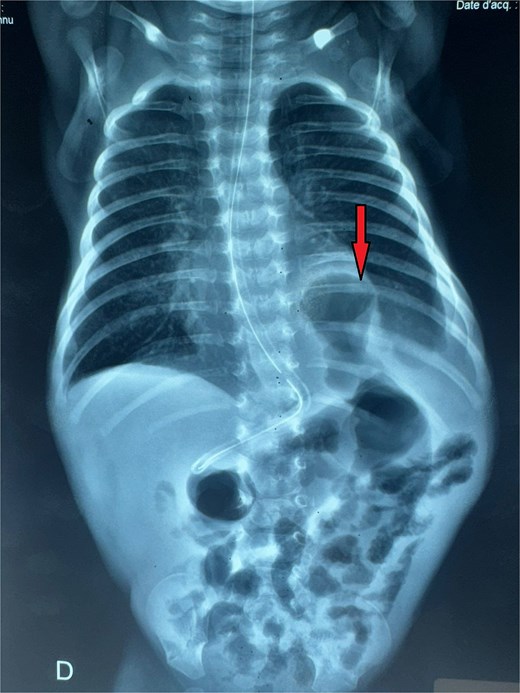

A male neonate was admitted at 47 h of life with signs of severe respiratory distress requiring immediate intubation. Physical examination revealed a distended abdomen, a prominent thoracic contour, and diminished breath sounds on the left side. A thoraco-abdominal X-ray showed multiple air-filled intestinal loops in the left hemithorax, consistent with a CDH. The patient underwent a primary repair of surgical repair of his diaphragmatic defect (Fig. 1). The initial postoperative course was complicated by multiple episodes of bowel obstruction. Postoperative radiographs demonstrated multiple air-fluid levels without evidence of significant colonic dilatation (Fig. 2). The patient underwent reoperations on postoperative days 21 and 50. Intraoperative findings revealed early adhesions without evidence of other anomalies. Adhesiolysis was performed on both occasions. The patient was discharged on postoperative day 60. At 3 months of age, the child was readmitted with signs of recurrent intestinal obstruction, including bilious vomiting, absence of stool and gas passage, and abdominal distension. The mother reported that spontaneous bowel movements occurred only after the administration of suppositories. Additionally, the child exhibited failure to thrive, with a weight below −2 standard deviations for age. The child had no facial dysmorphism or abnormalities of the limbs or nails.

Thoracoabdominal radiograph showing air-filled bowel loops within the thoracic cavity (arrow) with absent visualization of the diaphragmatic contour, consistent with a CDH.